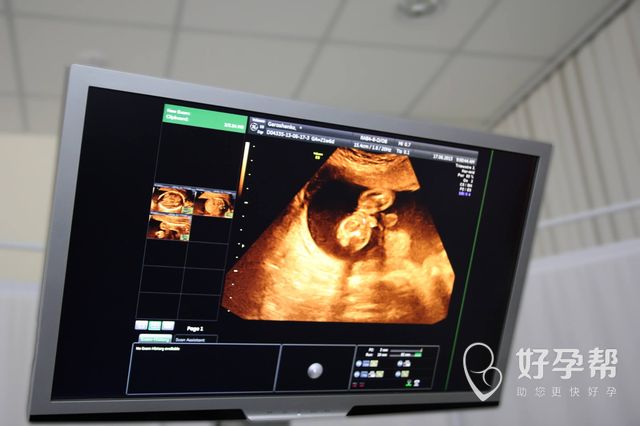

试管婴儿这项手术给患者带来更多孕育的希望,尤其针对不孕不育的患者来说,能够给他们解决更多问题,大多数的年轻患者在做这项手术的时候,希望自己能够拥有双胞胎,毕竟这能够缓解自己想要两个孩子的心态,同时还能够让自己免受第2胎的痛苦,所以说如果是年轻患者真的能够通过试管婴儿这项手术拥有双胞胎的话,这对他们来讲绝对是一举两得。

青岛试管婴儿双胞胎的价格相对于单胞胎会昂贵一些吗?这也是大多数患者希望能够了解的,其实从临床的诊断手术上来看,青岛试管婴儿双胞胎的价格和单胞胎的价格并没有太大的区别,只不过是在进行胚胎移植的过程当中,医生多移植一个胚胎,并不是说从性别上来进行筛选,所以说这对医生本身来讲并不会有太大的影响,因此他们的价格不会有太大差别,这一点患者完全可以放心。